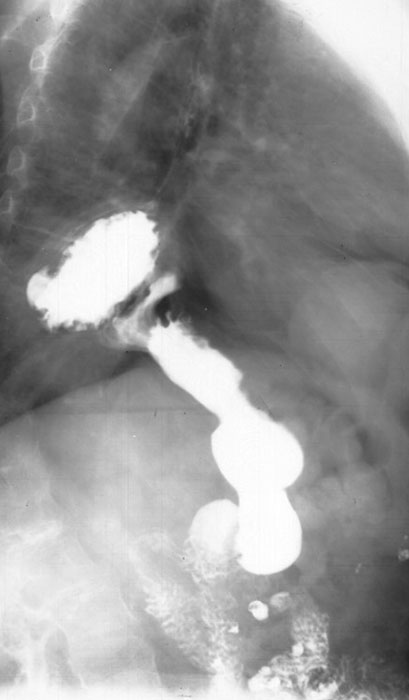

Bird’s beak sign, string sign, corkscrew esophagus.

What are the classic barium swallow signs of achalasia?